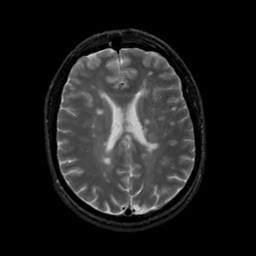

MR Study #19, August 25, 1991 -- Slice #31

[Home][Help][Clinical][Tour 1][Tour 2] Slice 31